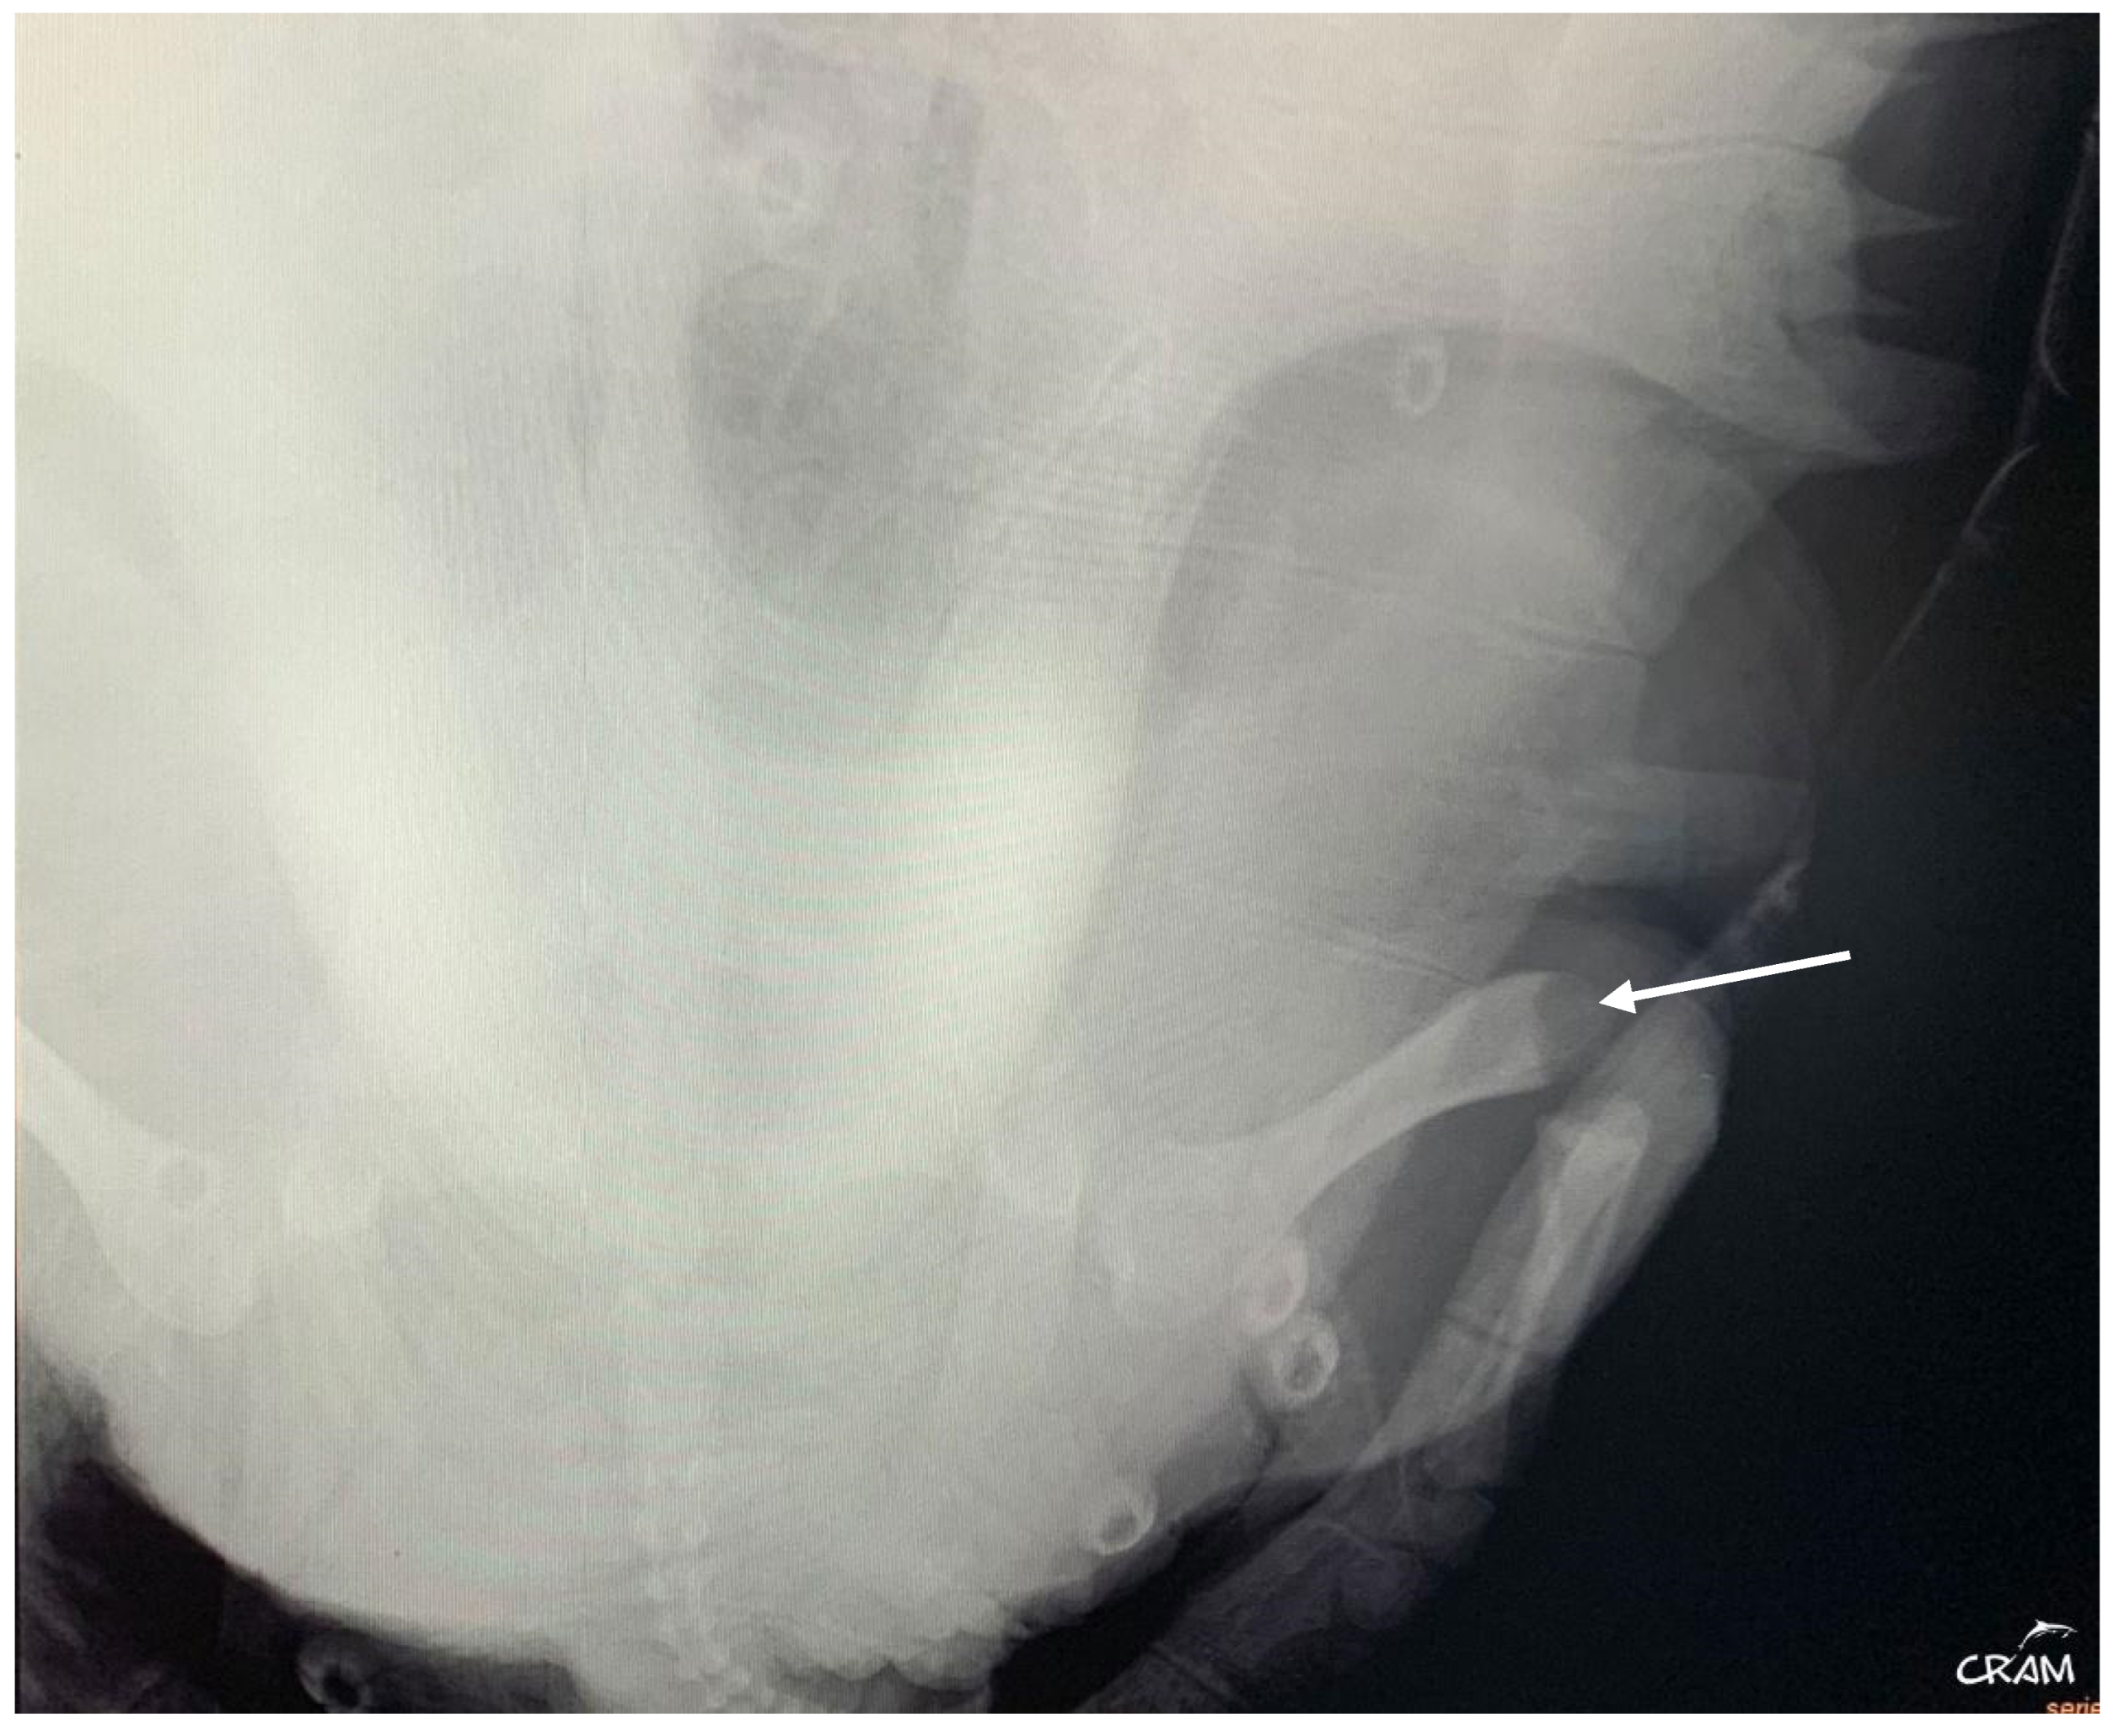

Hard edema with increased periarticular soft tissue and pain was noticed at palpation during clinical evaluation in veterinary medicine [21]. At the beginning of signs, radiographic lesions were polyostotic and poorly defined (Figure 5 and Figure 6).

Figure 6.

Right pelvic girdle in dorso-ventral view at day 45 of rehabilitation. Visible bone lysis on the distal end of the right femur (arrow).

Early-stage lesions at day 45 of rehabilitation were characterized by a purely osteolytic process restricted to the distal end of the humerus and femur and the proximal end of the radius, ulna, and tibia, including demineralization of the surrounding bones. Osteolytic lesions were restricted to the epiphysis and metaphysis of long bones, and no lesions were detected in the diaphysis.